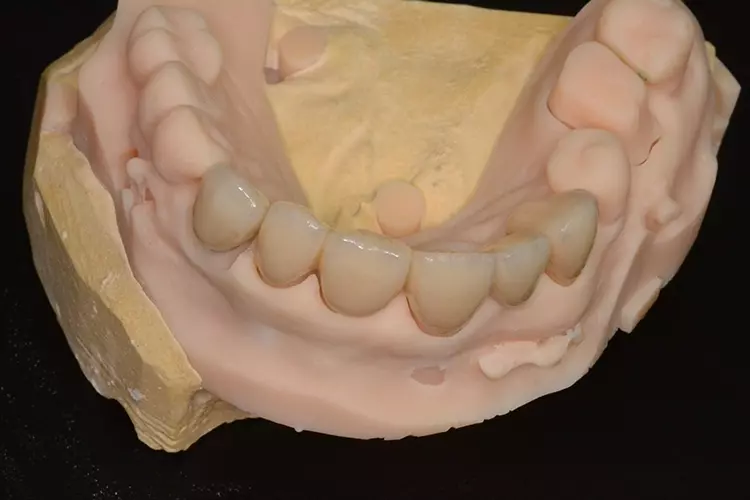

Grundlegend sollten zur Diagnostik und Befunderhebung zunächst Fotos der bestehenden Situation (Fotostatus in Okklusion links und rechts, Aufbiss Ober- und Unterkiefer) angefertigt werden. Außerdem ist anzuraten, ein Situationsmodell zu erstellen.

Auf diesem kann der Zahntechniker entweder durch Dublieren und Aufwachsen oder bei Verwendung eines Intraoralscanners auch digital, sowohl dem Zahnarzt als auch dem Patienten, einen Eindruck der zu erzielenden Situation vermitteln. Selbstverständlich muss auch eine genaue Röntgendiagnostik durchgeführt werden, d. h. mindestens Einzelzahnaufnahmen in Rechtwinkelparalleltechnik bzw. wenn auch operativ implantologisch versorgt werden soll, eine DVT-Diagnostik. In Zusammenhang mit den analogen oder digitalen Situationsmodellen kann mit vorliegendem DVT auch unkompliziert eine Bohrschablone hergestellt werden, um eine mögliche Implantation während der Behandlung navigiert durchführen zu können.

Dies kann bei den Seitenzähnen durchaus bei starken Abrasionen notwendig werden. In Fällen mit funktionellem Hintergrund, d. h. wo eine Erhöhung der Bisslage angestrebt wird, empfiehlt es sich, eine langzeitprovisorische Versorgung vorzunehmen. Wie bereits angesprochen, sollte in Zusammenarbeit mit dem zahntechnischen Labor schon im Vorab anhand von analogen oder digitalen Wax-ups dem Patienten ein Eindruck der neuen Situation verschafft werden.